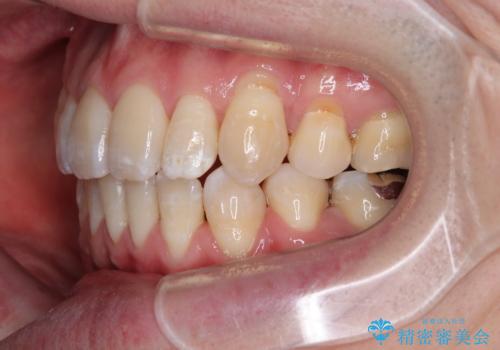

- 治療計画

- 「横から見ると唇が前に出て見えるのが気になる…」

「マスクを外すのが恥ずかしい…」

そんな口元の突出感に悩まれてご来院された患者様。

精密検査の結果、上下左右の小臼歯4本を抜歯し、そのスペースに前歯を後方へ移動させる矯正治療をご提案しました。